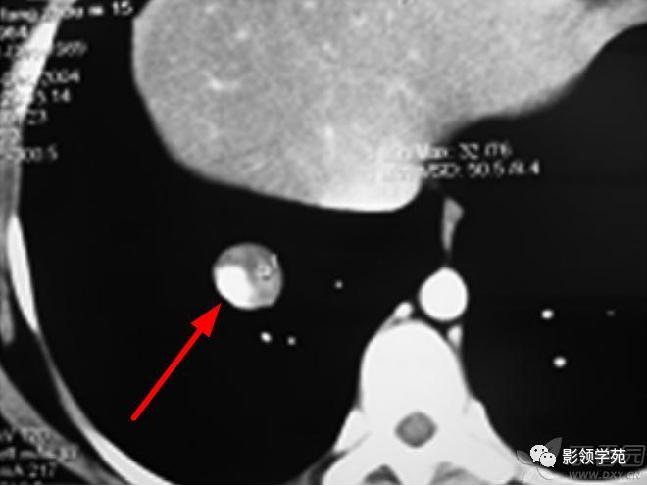

病例9:右下肺结节,病灶后份可见结节状钙化,边缘光滑,周围无卫星病灶。(钙化主要出现在治疗后肿块的边缘,相对较少见)

肺结核:肺Wegener肉芽肿的浸润性病灶为斑片状、絮状和粟粒状或单发的结节空洞时,与肺结核二者之间难以鉴别诊断,但肺结核患者常同时有低热、盗汗等结核中毒的临床症状,病变具有多发、多形、多钙化,病灶吸收消散慢的特点。病变好发于两肺上叶和下叶的背段,而Wegener肉芽肿病变范围广泛,各个肺野均可出现,缺乏规律性,结核球的密度较高,内部常有钙化,可有空洞,一般较小,洞壁较厚,壁内常见斑点状钙化,结节周围多出现斑点状和条索状“卫星灶”,肺内可有浸润性病变,但极少出现楔形阴影,因此,多数情况下能与结核鉴别。